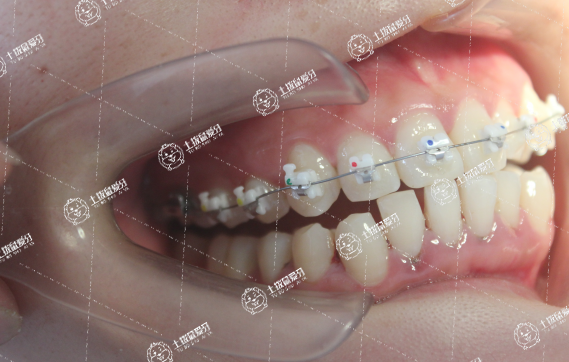

2.矯正方案制定:矯正器械通??煞譃楣潭ǔC治器與活動矯治器。醫(yī)生在了解患者總體情況后,會依據(jù)患者牙齒狀態(tài)制定詳細的牙齒地包天矯正治療方案,選擇適合患者的矯治器進行佩戴,以保證后續(xù)矯正治療的效果。

3.矯正后復查保持:通常患者達到牙齒地包天矯正治療效果,需要佩戴矯正器械1-3年左右。在治療期間,應當做好定期復查與保養(yǎng)工作,醫(yī)生會依據(jù)復查情況判斷矯正治療的效果,進而確定患者是否能夠摘下矯正器械。